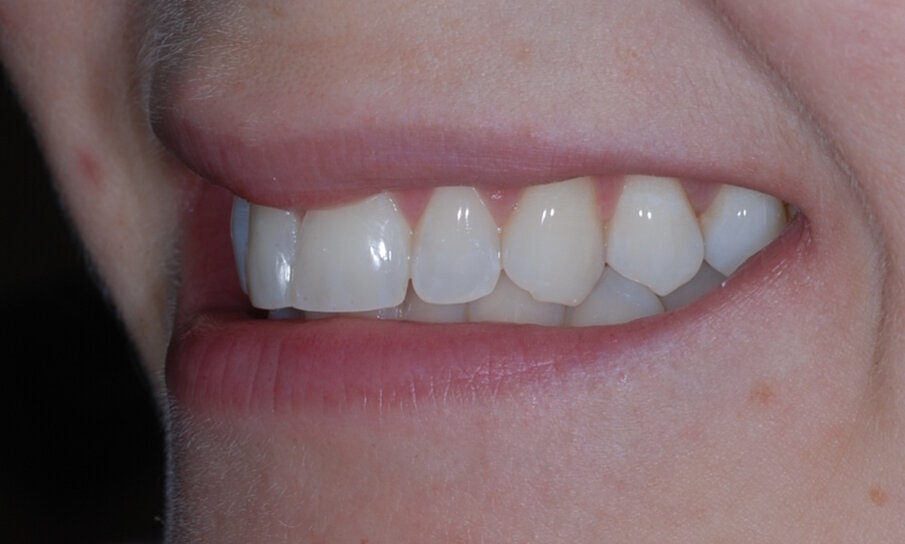

Fig. 2: Pre treatment right lateral

Fig. 16: Post treatment right lateral